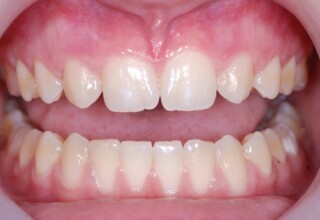

Restoration of bilateral diastemas between central and lateral incisors.

Diastemas were created mainly because of narrow laterals. After orthodontic treatment was finalized, the diastemas were closed with two composite resin restorations.